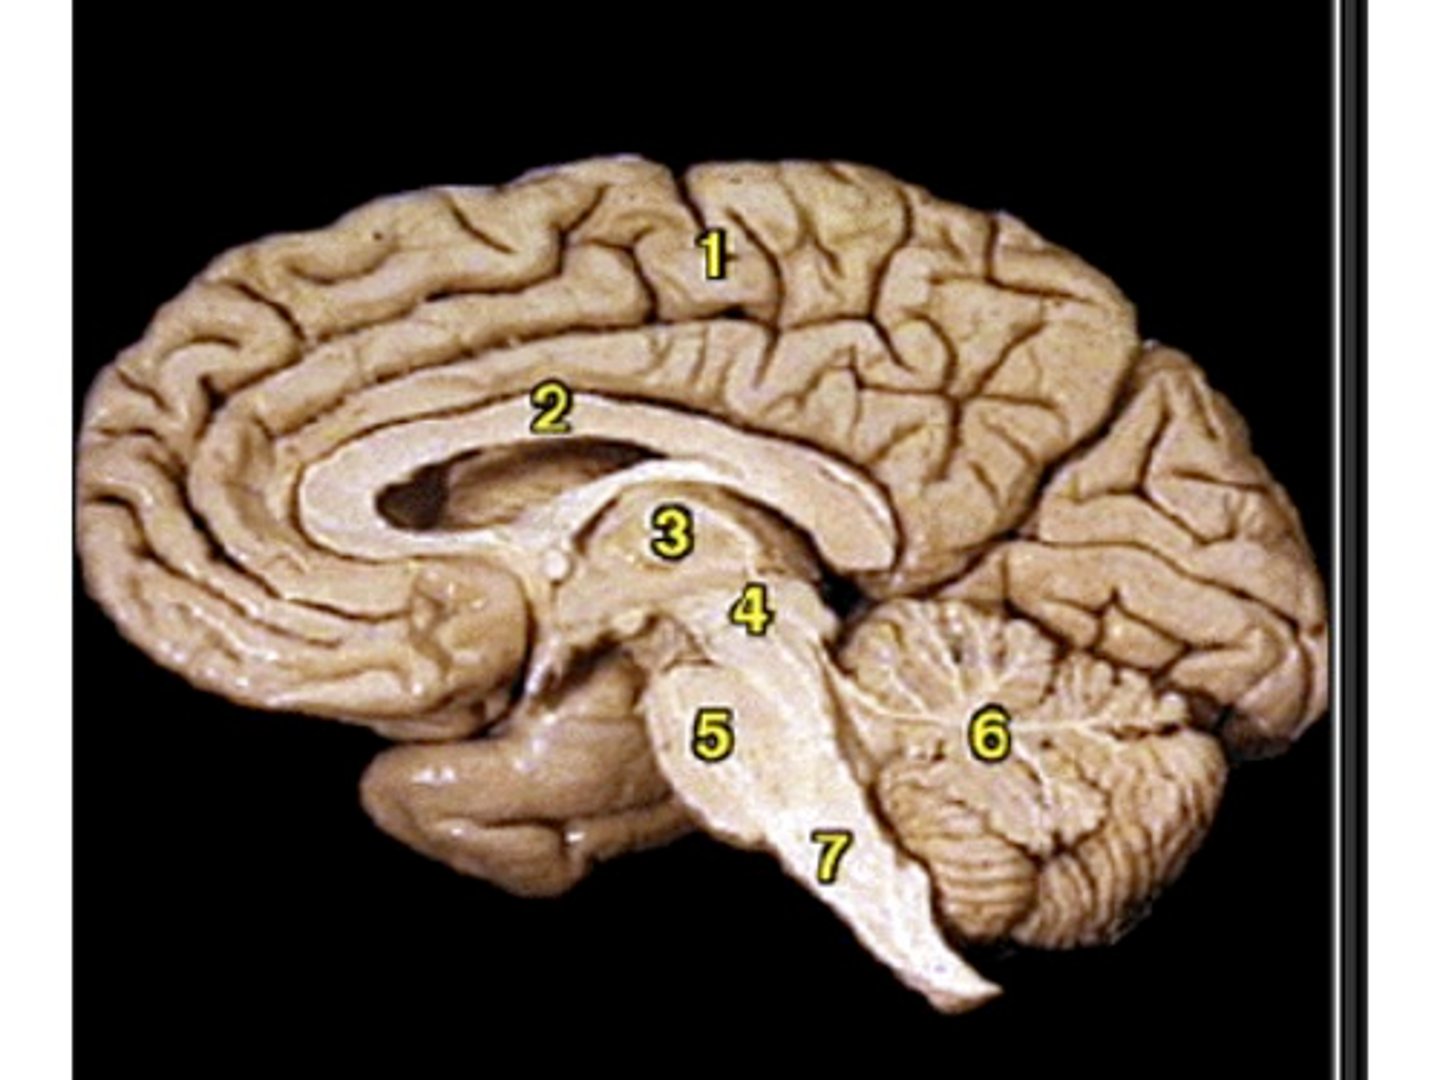

Sagittal View